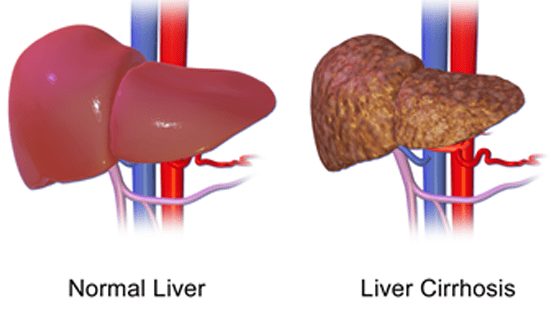

Non-Alcoholic Fatty Liver Disease is increasingly common worldwide and linked to obesity, diabetes, and metabolic syndrome. Recent research underscores that MASLD treatment centers on lifestyle modification and drug therapies targeted at metabolic risk factors.